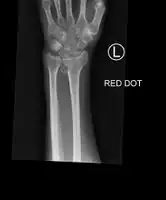

Colles fracture